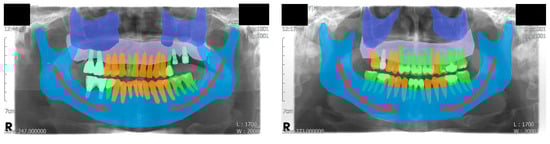

3.3. Evaluation with Semantic Segmentation Metrics

The metrics for pixel-level semantic segmentation, IoU and iIoU, were computed for each class and category. The iIoU was computed only for “things” and the corresponding category. In addition, a confusion matrix is presented to simplify the evaluation results (Figure 4). In the confusion matrix, each row represents the ground truth class, whereas each column represents the predicted class of the model. Each value in a cell represents a ratio of the number of pixels predicted by the model (as a class of the column among the pixels of the ground truth class) to the number of pixels of the ground truth class. A prior was computed for each row in the matrix, which represented a ratio of the number of pixels of the corresponding ground truth class to the total number of pixels. The confusion matrix and the IoU and iIoU for each class and category are shown in Figure 4, Table 2 and Table 3, respectively.

Figure 4.

Confusion matrix. Each row and column represents the ground truth class and the predicted class, respectively. Each cell represents the ratio of the number of predicted pixels (column class) among the ground truth pixels (row class) to the number of ground truth pixels. Priors were computed for each row to represent the ratio of the number of pixels in the corresponding ground truth class to the total number of pixels. UL, unlabeled class; Man, mandible; Max, maxilla; T_n, normal tooth; T_tx, treated tooth; Impl, dental implant.